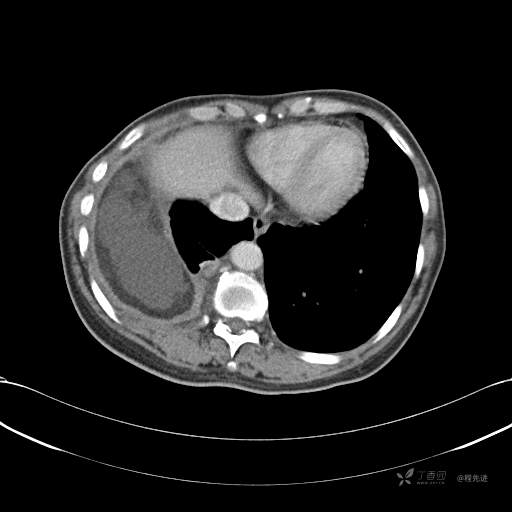

患者性别:女

患者年龄:51岁

简要病史:胸闷半年